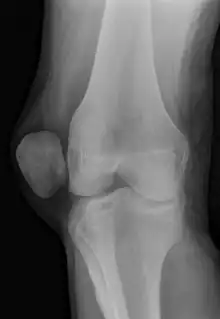

![]() | |

| X-ray showing a patellar dislocation, with the patella out to the side. | |